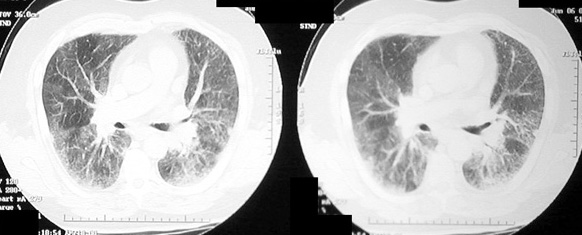

Amiadarone Toxicity